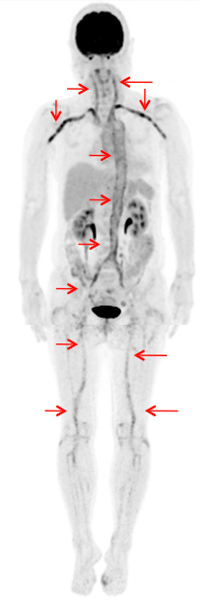

悪性リンパ腫

全身に広く分布する病変の活動性が一目で分かります。また高精度かつ早く撮影できる装置を導入していますので比較的短時間で頭から足先までの撮影が可能です。

治療前

多数の活動性病変を認めています。

治療後

異常集積は指摘できなくなっています。